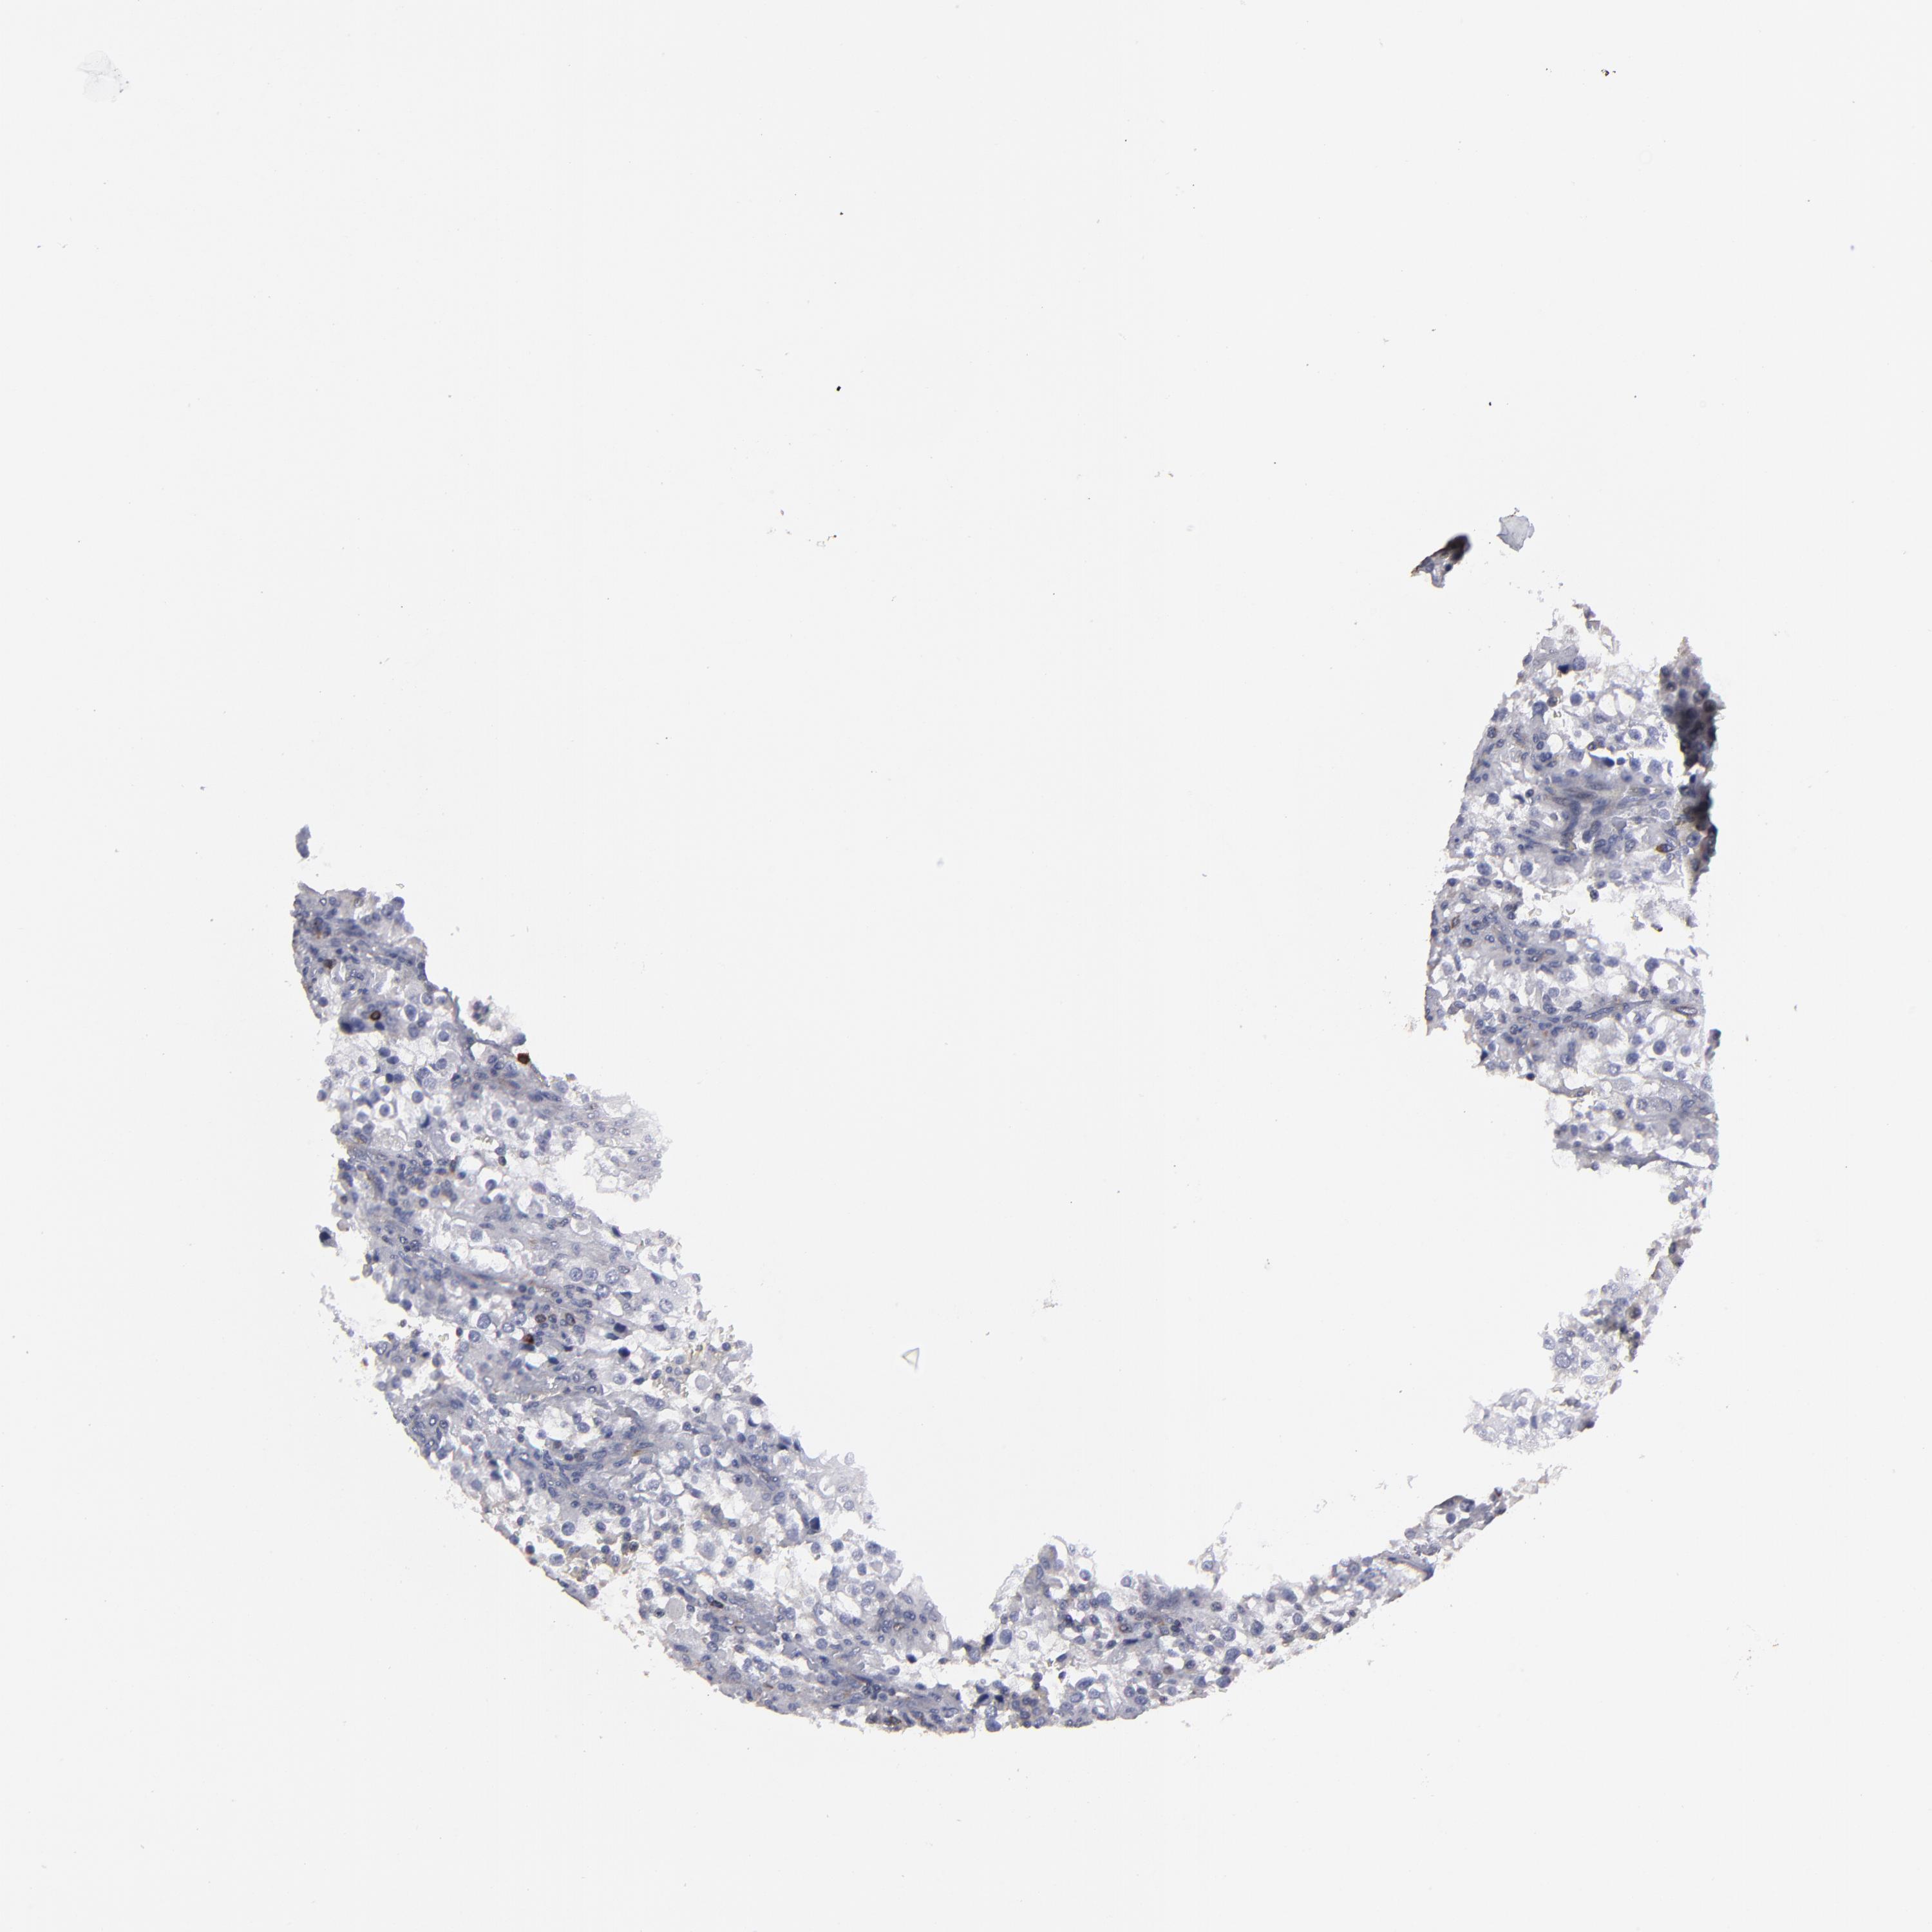

KIDNEY RENAL CLEAR CELL CARCINOMA (VALIDATION) - Interactive survival scatter ploti

The Survival Scatter plot shows the clinical status (i.e. dead or alive) for all individuals in the patient cohort, based on the same data that underlies the corresponding Kaplan-Meier plots. Patients that are alive at last time for follow-up are shown in blue and patients who have died during the study are shown in red.

The x-axis shows the expression levels (FPKM) of the investigated gene in the tumor tissue at the time of diagnosis. The y-axis shows the follow-up time after diagnosis (years). Both axes are complimented with kernel density curves demonstrating the data density over the axes. The top density plot shows the expression levels (FPKM) distribution among dead (red) and alive patients (blue). The right density plot shows the data density of the survived years of dead patients with high and low expression levels respectively, stratified using the cutoff indicated by the vertical dashed line through the Survival Scatter plot. This cutoff is automatically defined based on the FPKM cutoff that minimizes the p-score. The cutoff can be changed by dragging the vertical line or by entering a cutoff value in the square labeled "Current cut-off".

Under the Survival Scatter plot the p-score landscape (black curve; left axis) is shown together with dead median separation (red curve; right axis). Dead median separation is the difference in median mRNA expression between patients who have died with high and low expression, respectively. It is calculated as follows: median FPKM expression of dead patients with high expression - median FPKM expression of dead patients with low expression. This is intended to aid the user in visually exploring custom cutoffs and the associated p-scores and dead median separation.

Individual patient data is displayed and can be filtered by clicking on one or more of the category buttons on the top of the page. Categories describing expression level and patient information include: high, low, alive, dead, female, male and tumor stages. The scale of the x-axis can be toggled between linear and log-scale by clicking on the "x log" button. Mouse-over function shows TCGA ID, patient information and mRNA expression (FPKM) for each patient.

& Survival analysisi

Kaplan-Meier plots summarize results from analysis of correlation between mRNA expression level and patient survival. Patients were divided based on level of expression into one of the two groups "low" (under cut off) or "high" (over cut off). X-axis shows time for survival (years) and y-axis shows the probability of survival, where 1.0 corresponds to 100 percent.

CEP97 is not prognostic in Kidney Renal Clear Cell Carcinoma (validation)

: 3.01

Average pTPM 3.1

Number of samples 100